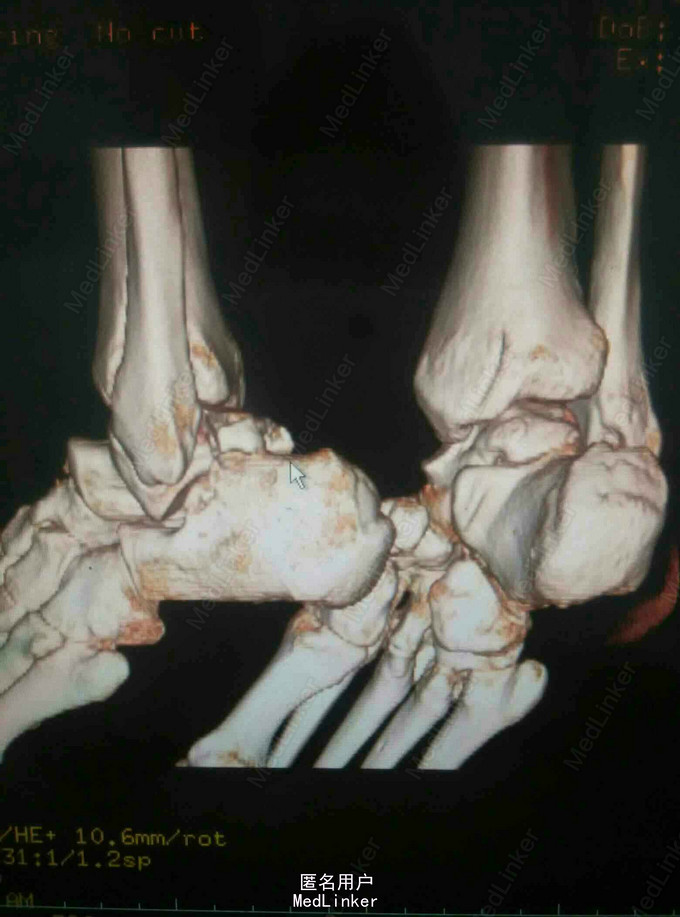

查体:左踝关节肿胀明显,局部皮肤压痛,无皮损及皮下淤斑,踝关节活动受限,各足趾感觉正常,足背动脉搏动存在。 辅查:我院CT提示距骨、足舟骨、跟骨骨折

诊断:左足距骨、足舟骨、跟骨骨折 治疗:距骨骨折切开复位内固定术

随访:石膏固定4-6周,3月内禁止负重,定期复查。 讨论:患者X线片对左足骨折显示不够清楚,基本常规行CT,可以看到明显的距骨骨折,累及关节面,需手术复位关节面。足舟骨以及跟骨骨折未明显移位保守处理。